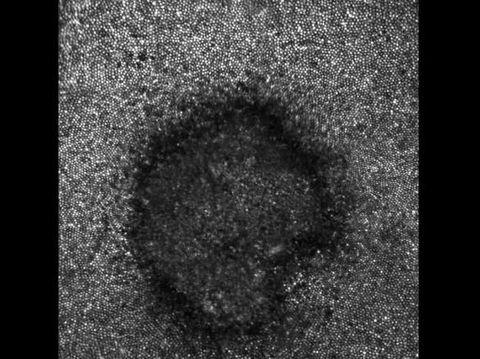

Foto: JAMA Ophthalmology |

Yang menarik adalah ketika tim dokter menggunakan teknologi baru bernama 'adaptive optics machine' untuk melihat seperti apa kerusakan yang dialaminya di level seluler. Ternyata sel-sel di retina Payne yang mengalami kerusakan tampak berbentuk bulan sabit juga.

"Ini mengingatkan kami saat ada pasien dengan kasus yang sama, kami minta mereka menggambarnya dan mereka menggambar bulan sabit. Ini sesuai dengan bentuk matahari yang memapari mereka sebelumnya. Tapi hal semacam ini tidak pernah bisa dilihat sebelumnya," ungkap Dr Avnish Deobhakta, dokter sekaligus penulis kasus ini.

Foto: JAMA Ophthalmology